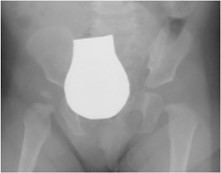

Come eseguire la radiografia per la displasia dell’anca?

- Proiezione Antero-Posteriore

- Paziente supino

- Arti allineati in asse perpendicolarmente al bacino

- Rotule allo zenith (in alto)

- Bacino parallelo al tavolo

- Nei bambini piccoli è presente un’ipertono flessorio delle anche: se si cerca di forzare l’estensione delle anche, il bacino ruota in antiversione e altera la proiezione. In questi casi, le anche vanno tenute in flessione (25-30°) con cuscini fino a pareggiare l’antiversione.

c) Che caratteristiche deve avere una radiografia del bacino eseguita correttamente?

- Bordi superiori dell’ Ischio e del Pube tangenti

- Ali iliache e forami otturatori simmetrici

- Cartilagine triradiata ben visibile

- Linea mediana del Sacro deve passare per la sinfisi pubica

- Bordo inferiore dell’ Ileo all’altezza dell’ultimo corpo sacrale

- Assi delle diafisi femorali: perpendicolari a linea di Hilgenreiner

Se l’esame non ha queste caratteristiche, si verificano degli “errori di incidenza” sui vari piani (x, y e z) che possono alterare il risultato dell’esame. Il radiologo nel giudicare una radiografia dovrà innanzitutto domandarsi se questa è stata eseguita correttamente e sia quindi giudicabile. Questo è soprattutto vero nel caso in cui dall’esito della radiografia dipenda una decisione terapeutica importante.